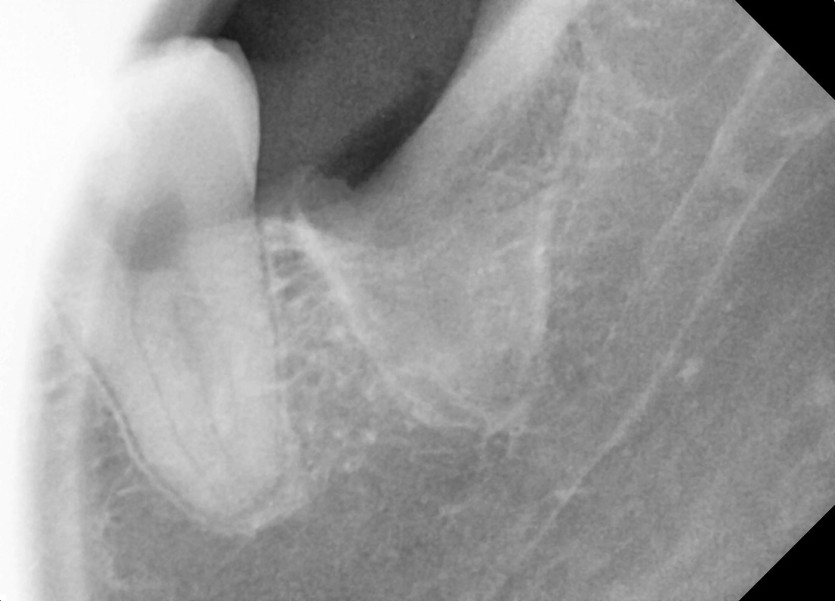

#18,28,38,48 사랑니 발치

구강 외과 전문의가 당일 발치했습니다.